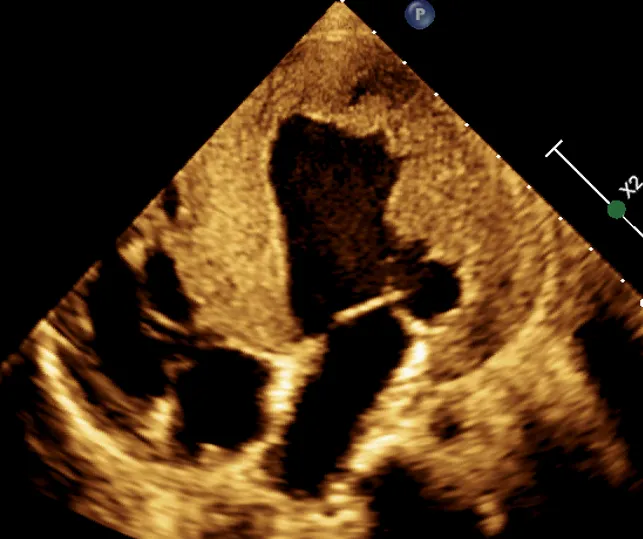

主要表现为心腔扩大,以左心扩大为主或全心扩大;左室球形变(图 2 ),室壁运动幅度弥漫性减低,相对室壁薄,瓣口开放幅度小,呈经典的「 大心腔、小开口 」改变。

图 2 四腔心切面显示,左室呈球形扩大